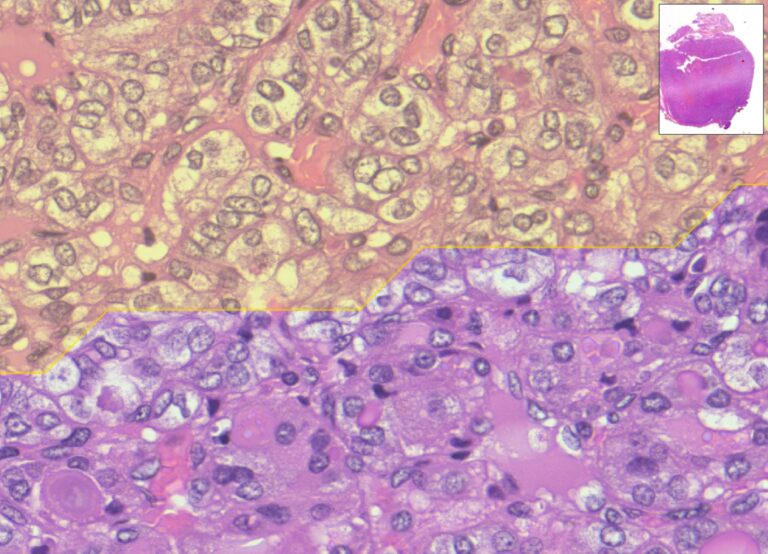

Il contesto è la patologia digitale, ovvero l’analisi di vetrini istologici digitalizzati con scanner molto potenti in grado di produrre “fotografie” dei campioni, in cui è possibile zoomare fino al livello delle singole cellule. La prima difficoltà è che la diagnosi dipende da valutazioni su scale molto diverse, che insieme possono discriminare tumori da altre patologie non invasive o meno aggressive. Il sistema sviluppato nella ricerca mette in campo due reti neurali che lavorano in sequenza: un primo “occhio digitale” coglie i dettagli delle cellule; un secondo “occhio” considera la visione d’insieme dell’immagine. Mettendo insieme le due letture, Mithyca indica dove conviene guardare prima.

Lo studio ha analizzato 73 immagini digitali di vetrini provenienti da più centri. Nei test il sistema ha indicato correttamente le aree di interesse in circa 8–9 casi su 10; per ogni vetrino ha impiegato pochi secondi. Le dimensioni dell’immagine non hanno influenzato in modo rilevante i tempi di calcolo.